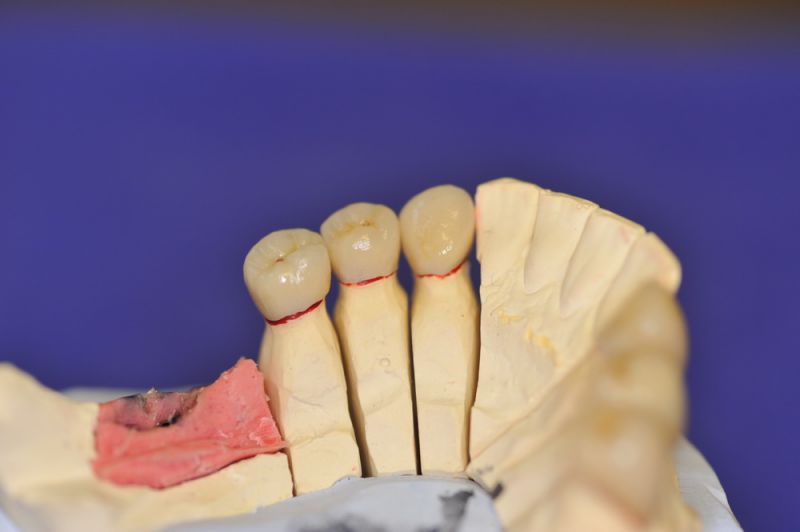

Mit dem heutigen Tag geht eine der technisch schwierigsten und anspruchsvollsten Arbeiten zu Ende, die im CMD-CENTRUM-KIEL jemals erstellt worden ist. Dabei sind es nur 10 Kronen, die benötigt werden, um die starken Kopf- und Gesichtsschmerzen der Patienten zu beseitigen.

4. Notwendigkeit die Mundhygienefähigkeit der Arbeit auch unter sehr beengten Verhältnissen zu schaffen, um der Arbeit eine günstige Prognose mitzugeben.